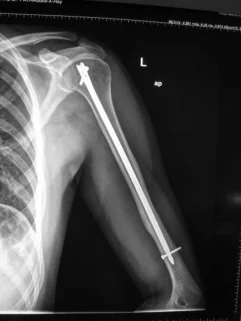

Humeral Shaft Fracture

- Management:

- Operative: (plate or IMN)

- Indications:

- Sever displaced Unreduced,

- Bilateral,

- multiple injuries

- floating elbow,

- Needs to use crutches

- Patients’ preference (active, athlete)